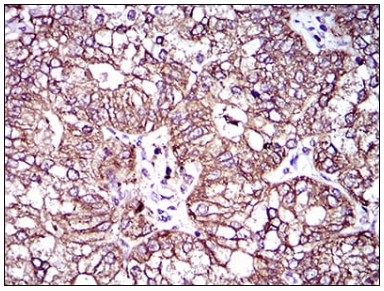

IHC    1/200 - 1/1000